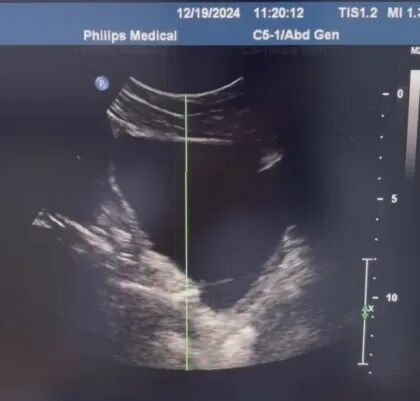

超声定位结石。

2022年10月,烟台山医院启用泌尿碎石中心。在过去两年多的时间里,体外冲击波碎石技术以其无创非侵入性和高效安全性,在治疗泌尿系统结石领域发挥了重要作用,为广大尿路结石患者提供了安全、高效、经济的治疗选择。烟台山医院的体外冲击波碎石治疗系统具备超声、X线双定位功能,兼顾X线阴性以及阳性结石,能够更加清晰、准确评估结石的大小、位置及数量;同时,在治疗实施过程中,可以根据评估结果个体化确定适合的冲击波强度和频率,达到精确高效的碎石效果。治疗持续时间大约为20到30分钟,不需要麻醉,疗程结束后,大多数患者可以立即返回日常生活。这种技术不仅显著降低了治疗风险,缩短了治疗时间,还减少了术后恢复时间,疗程花费少,对患者而言,既减轻了痛苦,又安全、经济、高效。